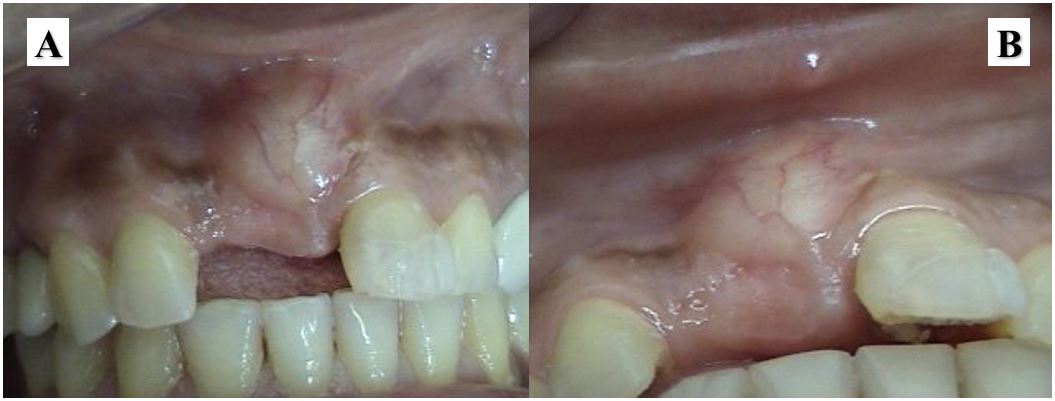

Se realizó el control y retiro de los puntos de sutura 10 días después del procedimiento. En el paladar y en el sitio receptor se observó una cicatrización sin complicaciones. Se retiraron los puntos de sutura. La paciente asistió a controles durante el primer año. Regresó a consulta a los siete años y presentaba clínicamente un sobrecrecimiento redondeado de aproximadamente 1 cm de diámetro, consistencia dura, color rosado pálido, sin signos de inflamación gingival y compatible con exostosis en el sitio donde se colocó el injerto. La paciente refirió que dicho crecimiento se fue dando con el paso del tiempo y que la afectaba estéticamente (figura 4).

a) imagen vestibular. b) imagen oclusal

Fuente: elaboración propia.Después de la firma del consentimiento informado por parte de la paciente, se le realizó una osteoplastia, a fin de tomarle una muestra para analizarla histopatológicamente y mejorar la estética de la zona. Se realizó una incisión paracrestal del 12 al 22 con incisiones relajantes mesial y distal, se elevó un colgajo mucoperióstico y se encontró un tejido duro de aspecto similar al hueso. Con la osteoplastia de la zona afectada se redujo el tamaño de la lesión y se tomó una biopsia tanto del área de la exostosis como del tejido blando, las cuales se enviaron a análisis histopatológico. Se remitieron cuatro fragmentos de 1,5 cm de tejido óseo de aspecto sano y cuatro fragmentos del tejido blando de 0,3 cm × 0,6 cm. Se encontró que el tejido óseo presentaba cambios de hiperostosis consistentes en aumento del grosor de la capa de hueso compacto y de la densidad del hueso trabecular, sin ninguna evidencia de transformación maligna, y compatible con exostosis ósea. El tejido blando tenía tejido epitelial y conectivo de aspecto normal (figura 5).